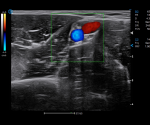

Radiology

· CHI visualizes blood perfusion status in real-time with high image contrast to detect micro lesions and outline tumor.